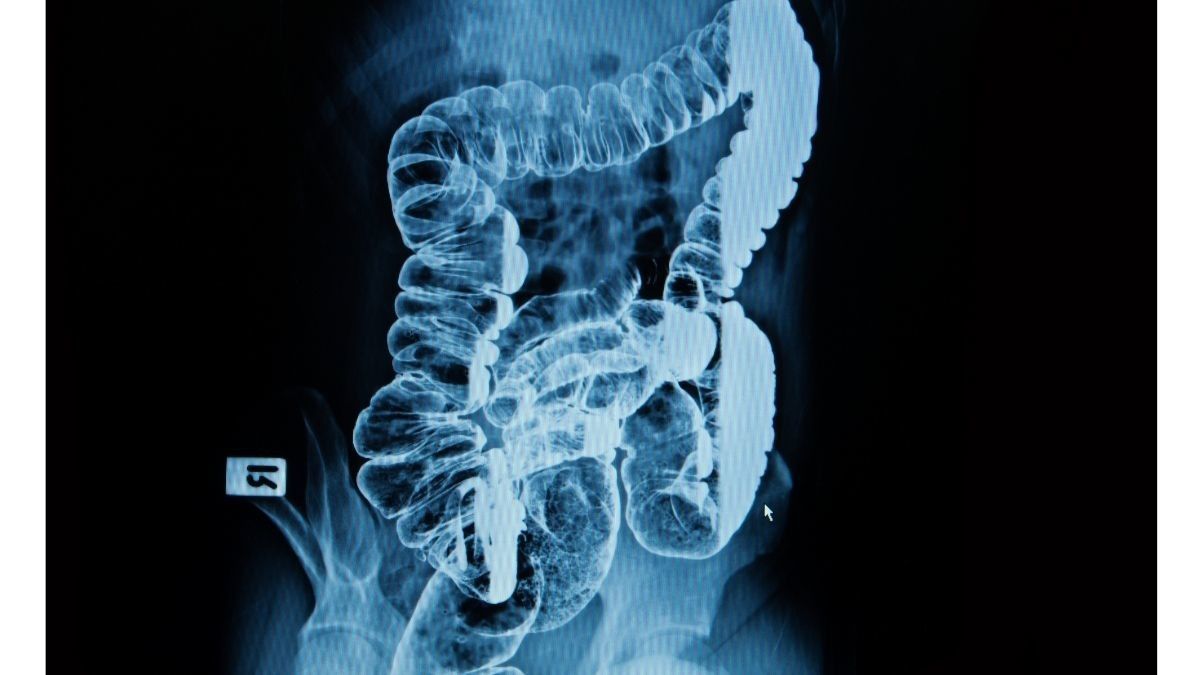

Barium enema adalah pemeriksaan X-ray yang bisa mendeteksi adanya kelainan atau perubahan di kolon atau usus besar. Prosedur ini disebut juga dengan colon X-ray.

Enema adalah penyuntikan berisi cairan tertentu melalui tabung kecil. Dalam pemeriksaan barium enema, enema yang berisi zat barium akan disuntikkan ke rektum.

Barium enema digunakan untuk memeriksa penyebab dari gejala pada perut. Dokter biasanya menganjurkan pemeriksaan barium enema jika dicurigai adanya kelainan pada saluran pencernaan bagian bawah.